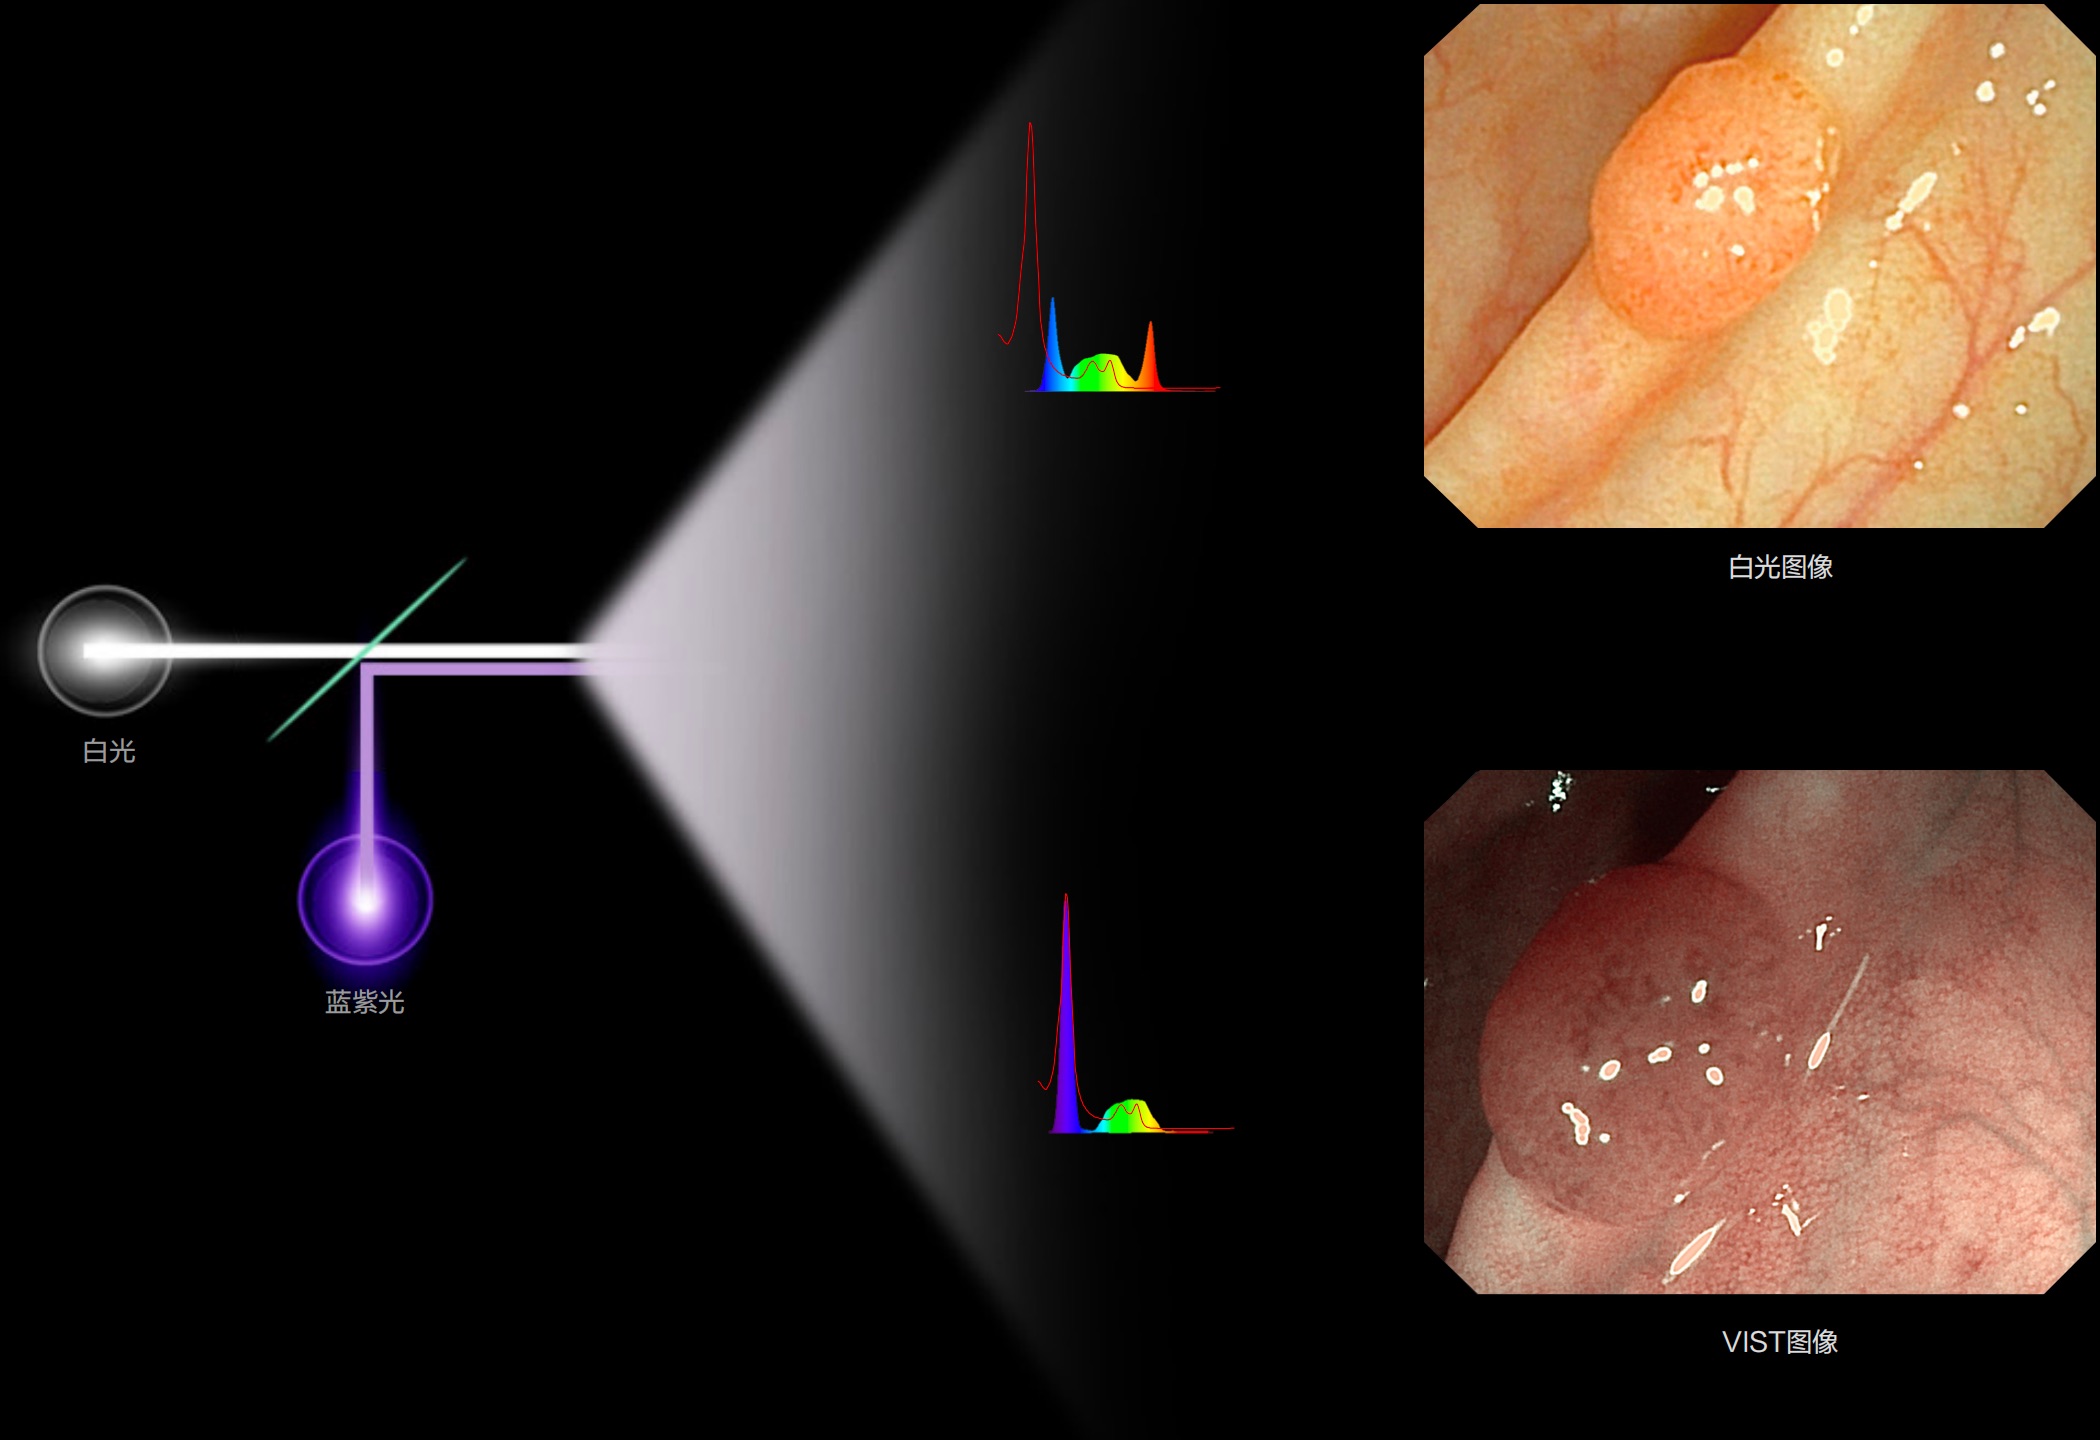

(Versatile Intelligent Staining Technology)

能够凸显黏膜浅层血管轮廓和黏膜表面微结构,适用于中、近景观察下的早癌精确诊断。

白光图像